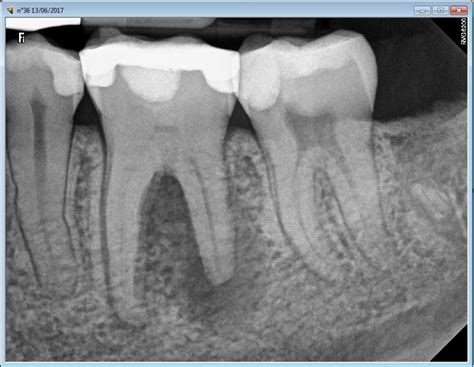

How is calcified tooth root diagnosed?

Calcified tooth root can be diagnosed through a dental exam and X-rays. The X-ray will show the extent of the calcification and help the dentist determine the best course of treatment.